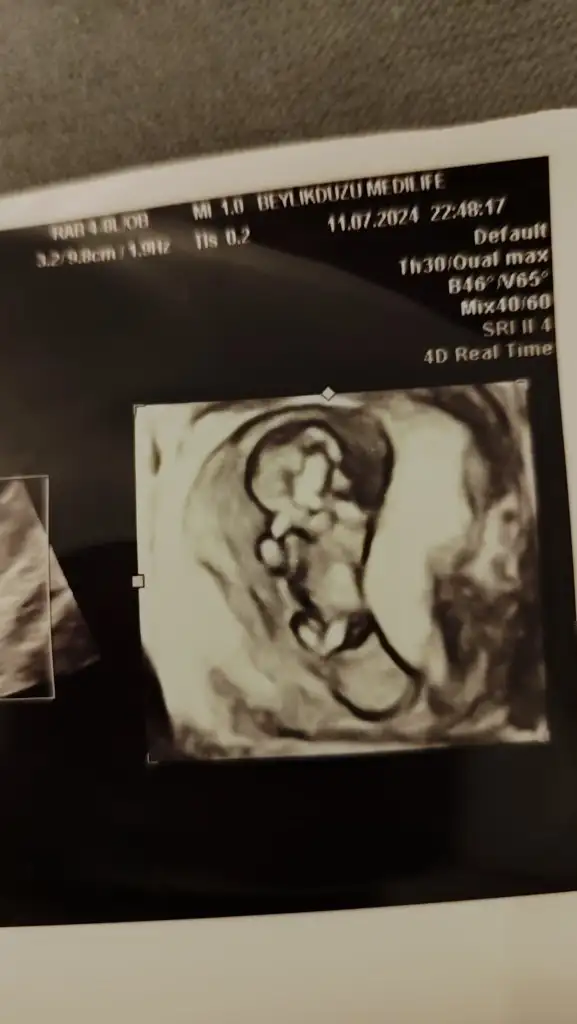

Evet öğrendik , oğluşumuz geliyorcinsiyeti öğrendiniz mi

Tamam canım teşekkürlerEvet öğrendik , oğluşumuz geliyor